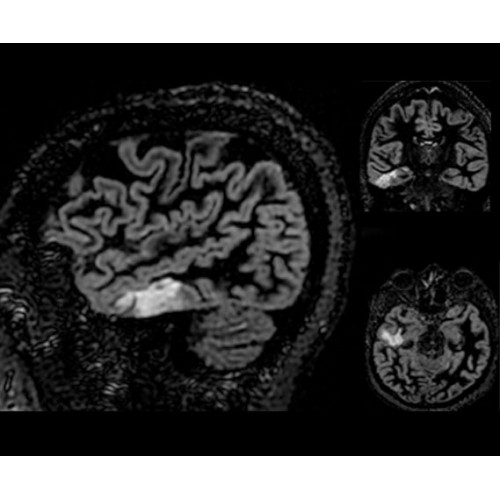

• Специальный пакет приложений для измерения и сравнения объемных изображений ЦНС с нормами поможет вам в диагностике нейродегенеративных заболеваний, а дополнительные инструменты визуализации — в постановке точного диагноза с помощью бета-амилоидов и радиоизотопных маркеров ФДГ.

Кроме того, в результате использования технологии TOF и инновационной технологии реконструкции Q.Clear вы сможете добиться прекрасного соотношения сигнал/шум. А благодаря технологии нулевого времени эхо (ZTE) визуализировать костную структуру без ионизирующего излучения. Все эти разработки для улучшения качества сканирования и точности анализа помогут вам использовать весь потенциал ПЭТ/МРТ.

• Q.Clear — в основу технологии легли накопленные знания о том, как минимизировать помехи при реконструкции и получить четкое изображение. При значительном улучшении качества изображения сохраняется точность расчетов. Сочетание технологии TOF и реконструкции Q.Clear — ваш надежный помощник для получения точных и достоверных данных.

• МРТ с функцией нулевого времени эхо (ZTE) отличается точностью, возможностью персональных настроек и отсутствием ионизирующего излучения. Она приходит на смену традиционному исследованию на основе рентгеновского излучения. МРТ с функцией нулевого времени эхо (ZTE) на базе SIGNA ПЭТ/МРТ является более надежной и быстрой по сравнению с системами, использующими сверхмалое время эхо (UTE).